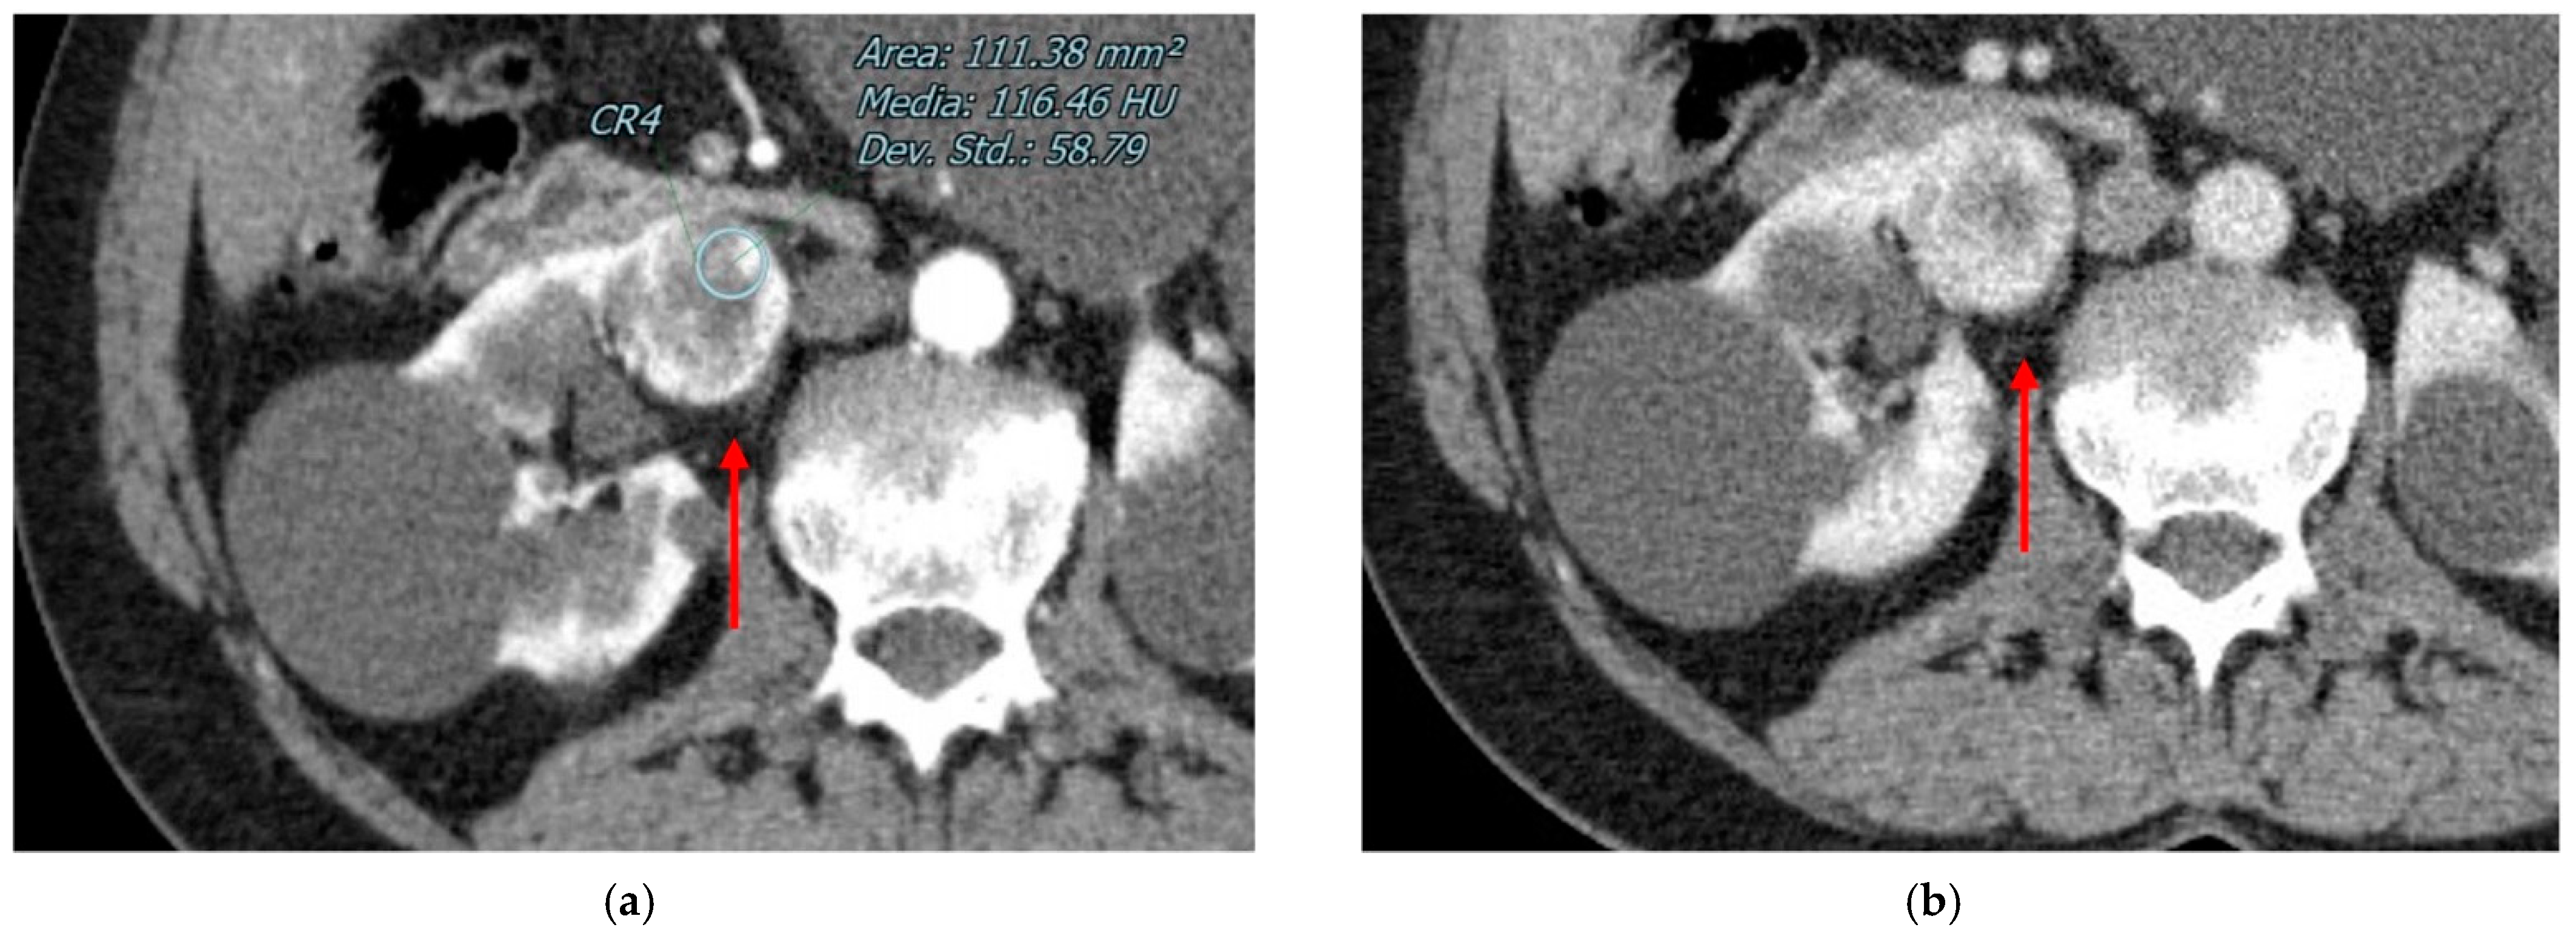

2.1. Angiomyolipomas

3.1. Clear Cell RCC